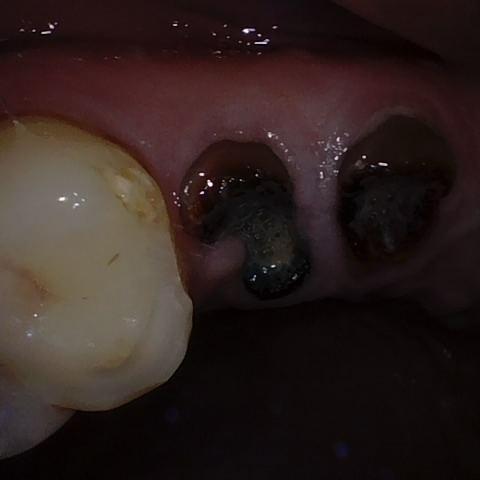

Annotated as "Good"